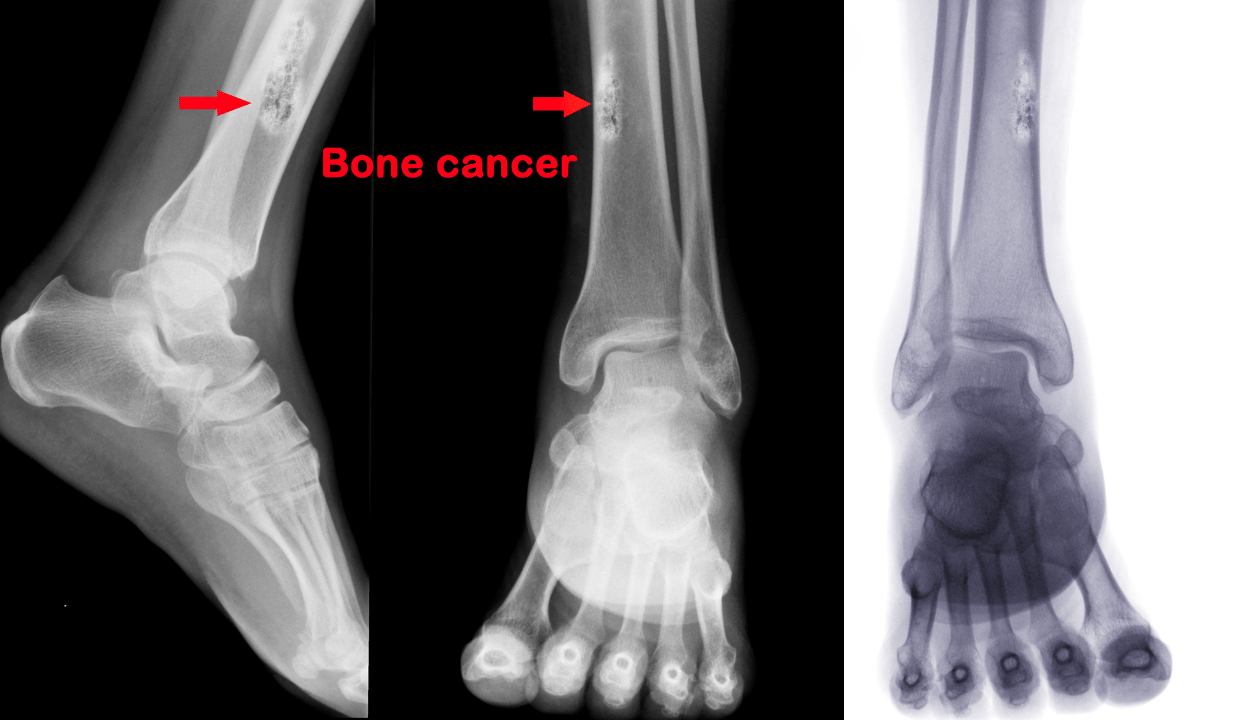

| Рентгенографическое исследование | Быстрый и доступный метод диагностики, позволяющий увидеть структуру кости | Обнаружение опухолевых образований, их размера и формы |